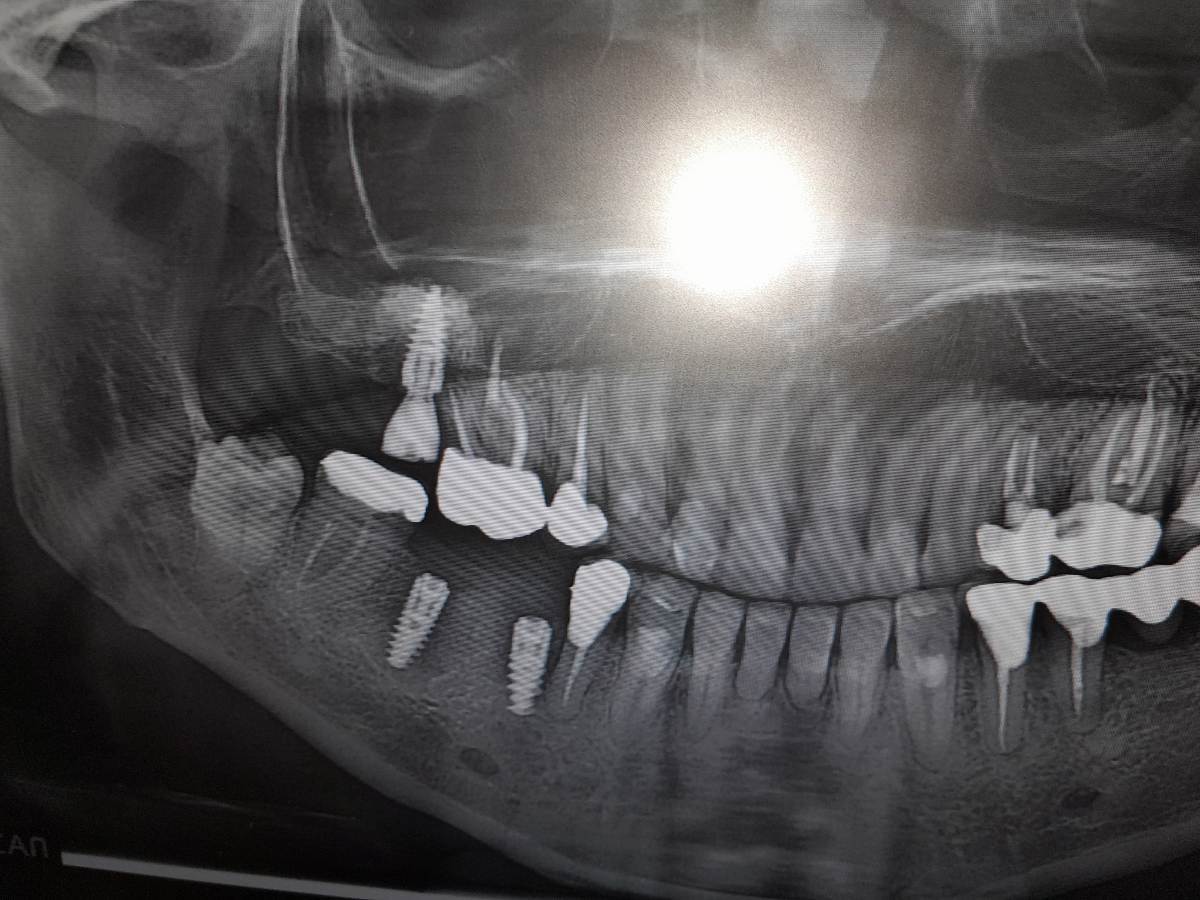

Irina xyz Опубликовано 17 ноября, 2025 Поделиться Опубликовано 17 ноября, 2025 (изменено) 26 окт поставили имплант на 45 29 окт заболел 44 Решили "попробовать" авось пройдет (врач решил) Попробовали Острая боль прошла, чувствительность 44го сохранилась 16 ноября распухла десна Снимок сделан сегодня Здесь снимок от 26го окт Решили еще "попробовать" Вскрыли, поставили теперь формирователь (?).. а вдруг поможет... Есть большие сомнения Отсюда вопрос Можт лучше просто удалить имплант и потом как врсстановится переделать? ... потому что имплант очевидно слишком близко к 44 му зубу и там меньше миллиметра намвыходе между фармирователем и 44м . Изменено 17 ноября, 2025 пользователем Irina xyz . Ссылка на комментарий

Irina xyz Опубликовано 17 ноября, 2025 Автор Поделиться Опубликовано 17 ноября, 2025 Еще один снимок от сегодня - не фонит Ссылка на комментарий

Irina xyz Опубликовано 17 ноября, 2025 Автор Поделиться Опубликовано 17 ноября, 2025 То есть то что так близко к 44му - это нормально? Его бы на 0 5-1 мм бы подвинуть от 44 особенно в нижней части .. есть ощущение что имплант на грани кости и тканей вокруг зуба.. отого и 44 реагирует.. Нет? Ссылка на комментарий

сирена Опубликовано 18 ноября, 2025 Поделиться Опубликовано 18 ноября, 2025 44 реагирует от воспаления(периимплантита), имплант надо удалить и месяца через 3 переставить. Задержите протезирование, но зато с хорошим прогнозом. Там нет экстремальной близости к зубу, просто так получилось, что именно этот воспалился. Бывает такое. 1 1 Ссылка на комментарий

Irouil Опубликовано 20 ноября, 2025 Поделиться Опубликовано 20 ноября, 2025 Проще всего имплант удалить, сразу можно будет и проверить причину боли - он или зуб. Если не поможет удаление импланта - надо бф перелечить/удалить зуб Но очевидных показаний к удалению я не вижу, есть деминерализация костной ткани вокруг, может быть признаком "отторжения", а может и пройти (и установка формирователя выглядит тут разумной мерой в попытке спасения импланта) Я бы удалил, но часть решения лежит и на Ваших плечах Ссылка на комментарий